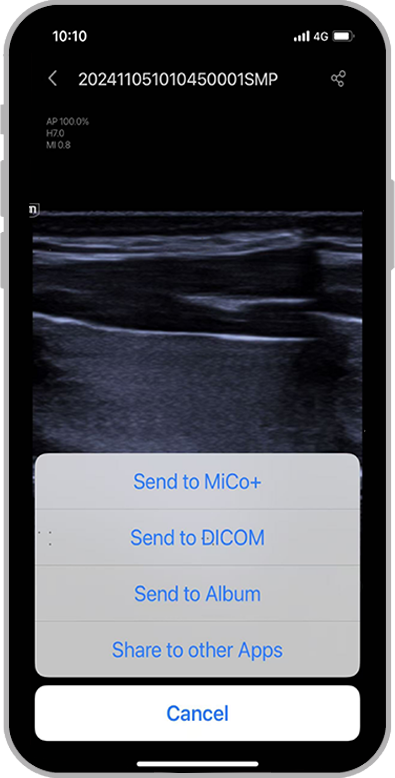

- Ajuda remota: solu??o de colabora??o da Mindray

O TE Air e o Mico+ trabalham juntos realizar o compartilhamento em tempo real de exames de ultrassom, incluindo imagens, ĂĄudio e vĂdeo, para o dispositivo terminal, para orienta??o, treinamento, controle de qualidade, discuss?es de casos e muito mais

Compartilhamento com um clique